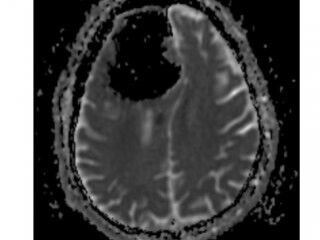

Doktorlar röntgene baktığında beynin sağ tarafında 9 santimlik siyah bir görüntü gördü. Doktorlar, 84 yaşındaki hastanın sağ ön lobunun olmadığını fark etti.

Doktorlar hastanın pnömatosel rahatsızlığı ( akciğerde kistik hava boşluğu) olduğu için beyin dokusuna zarar verdiği görüşünde birleşti.